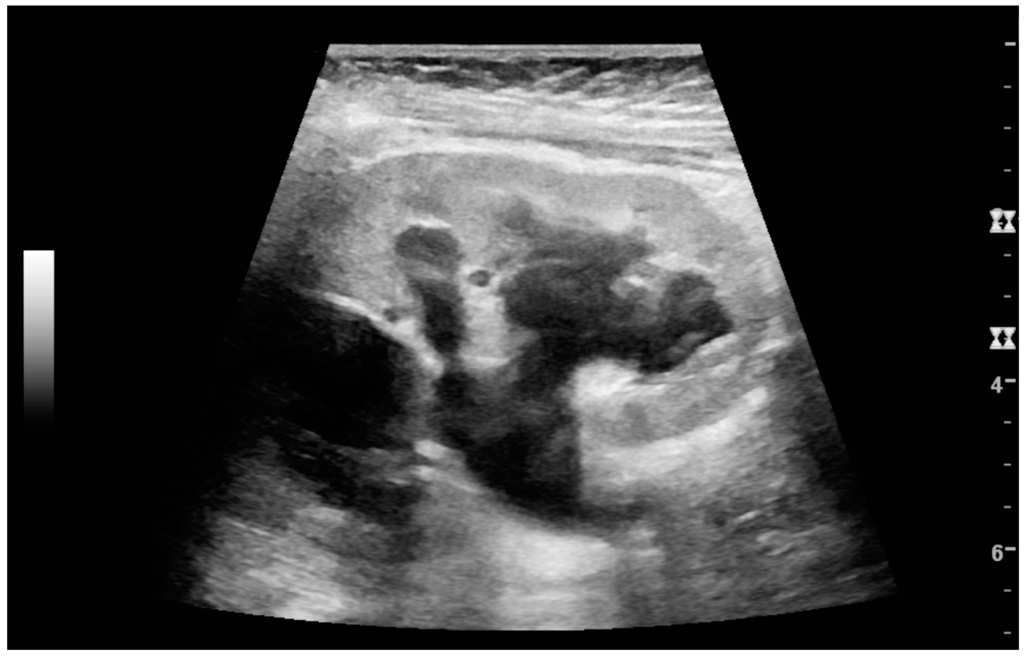

A solid renal mass appears in the US exam with internal echoes, without the well-defined, smooth walls seen in cysts, often with Doppler signal, and is frequently malignant or has a high malignant potential [4]. The most common malignant renal parenchymal tumor is renal cell carcinoma (RCC), which accounts for 86% of the malignancies in the kidney [2]. RCCs are typically isoechoic and peripherally located in the parenchyma, but can be both hypo- and hyper-echoic and are found centrally in medulla or sinus. The lesions can be multifocal and have cystic elements due to necrosis, calcifications and be multifocal (Figure 8 and Figure 9) [2]. RCC is associated with von Hippel–Lindau disease, and with tuberous sclerosis, and US has been recommended as a tool for assessment and follow-up of renal masses in these patients [18].

Figure 9. Renal cell carcinoma with both cystic and solid components located in the cortex. Measurement of tumor on the US image is illustrated by ‘+’ and a dashed line.